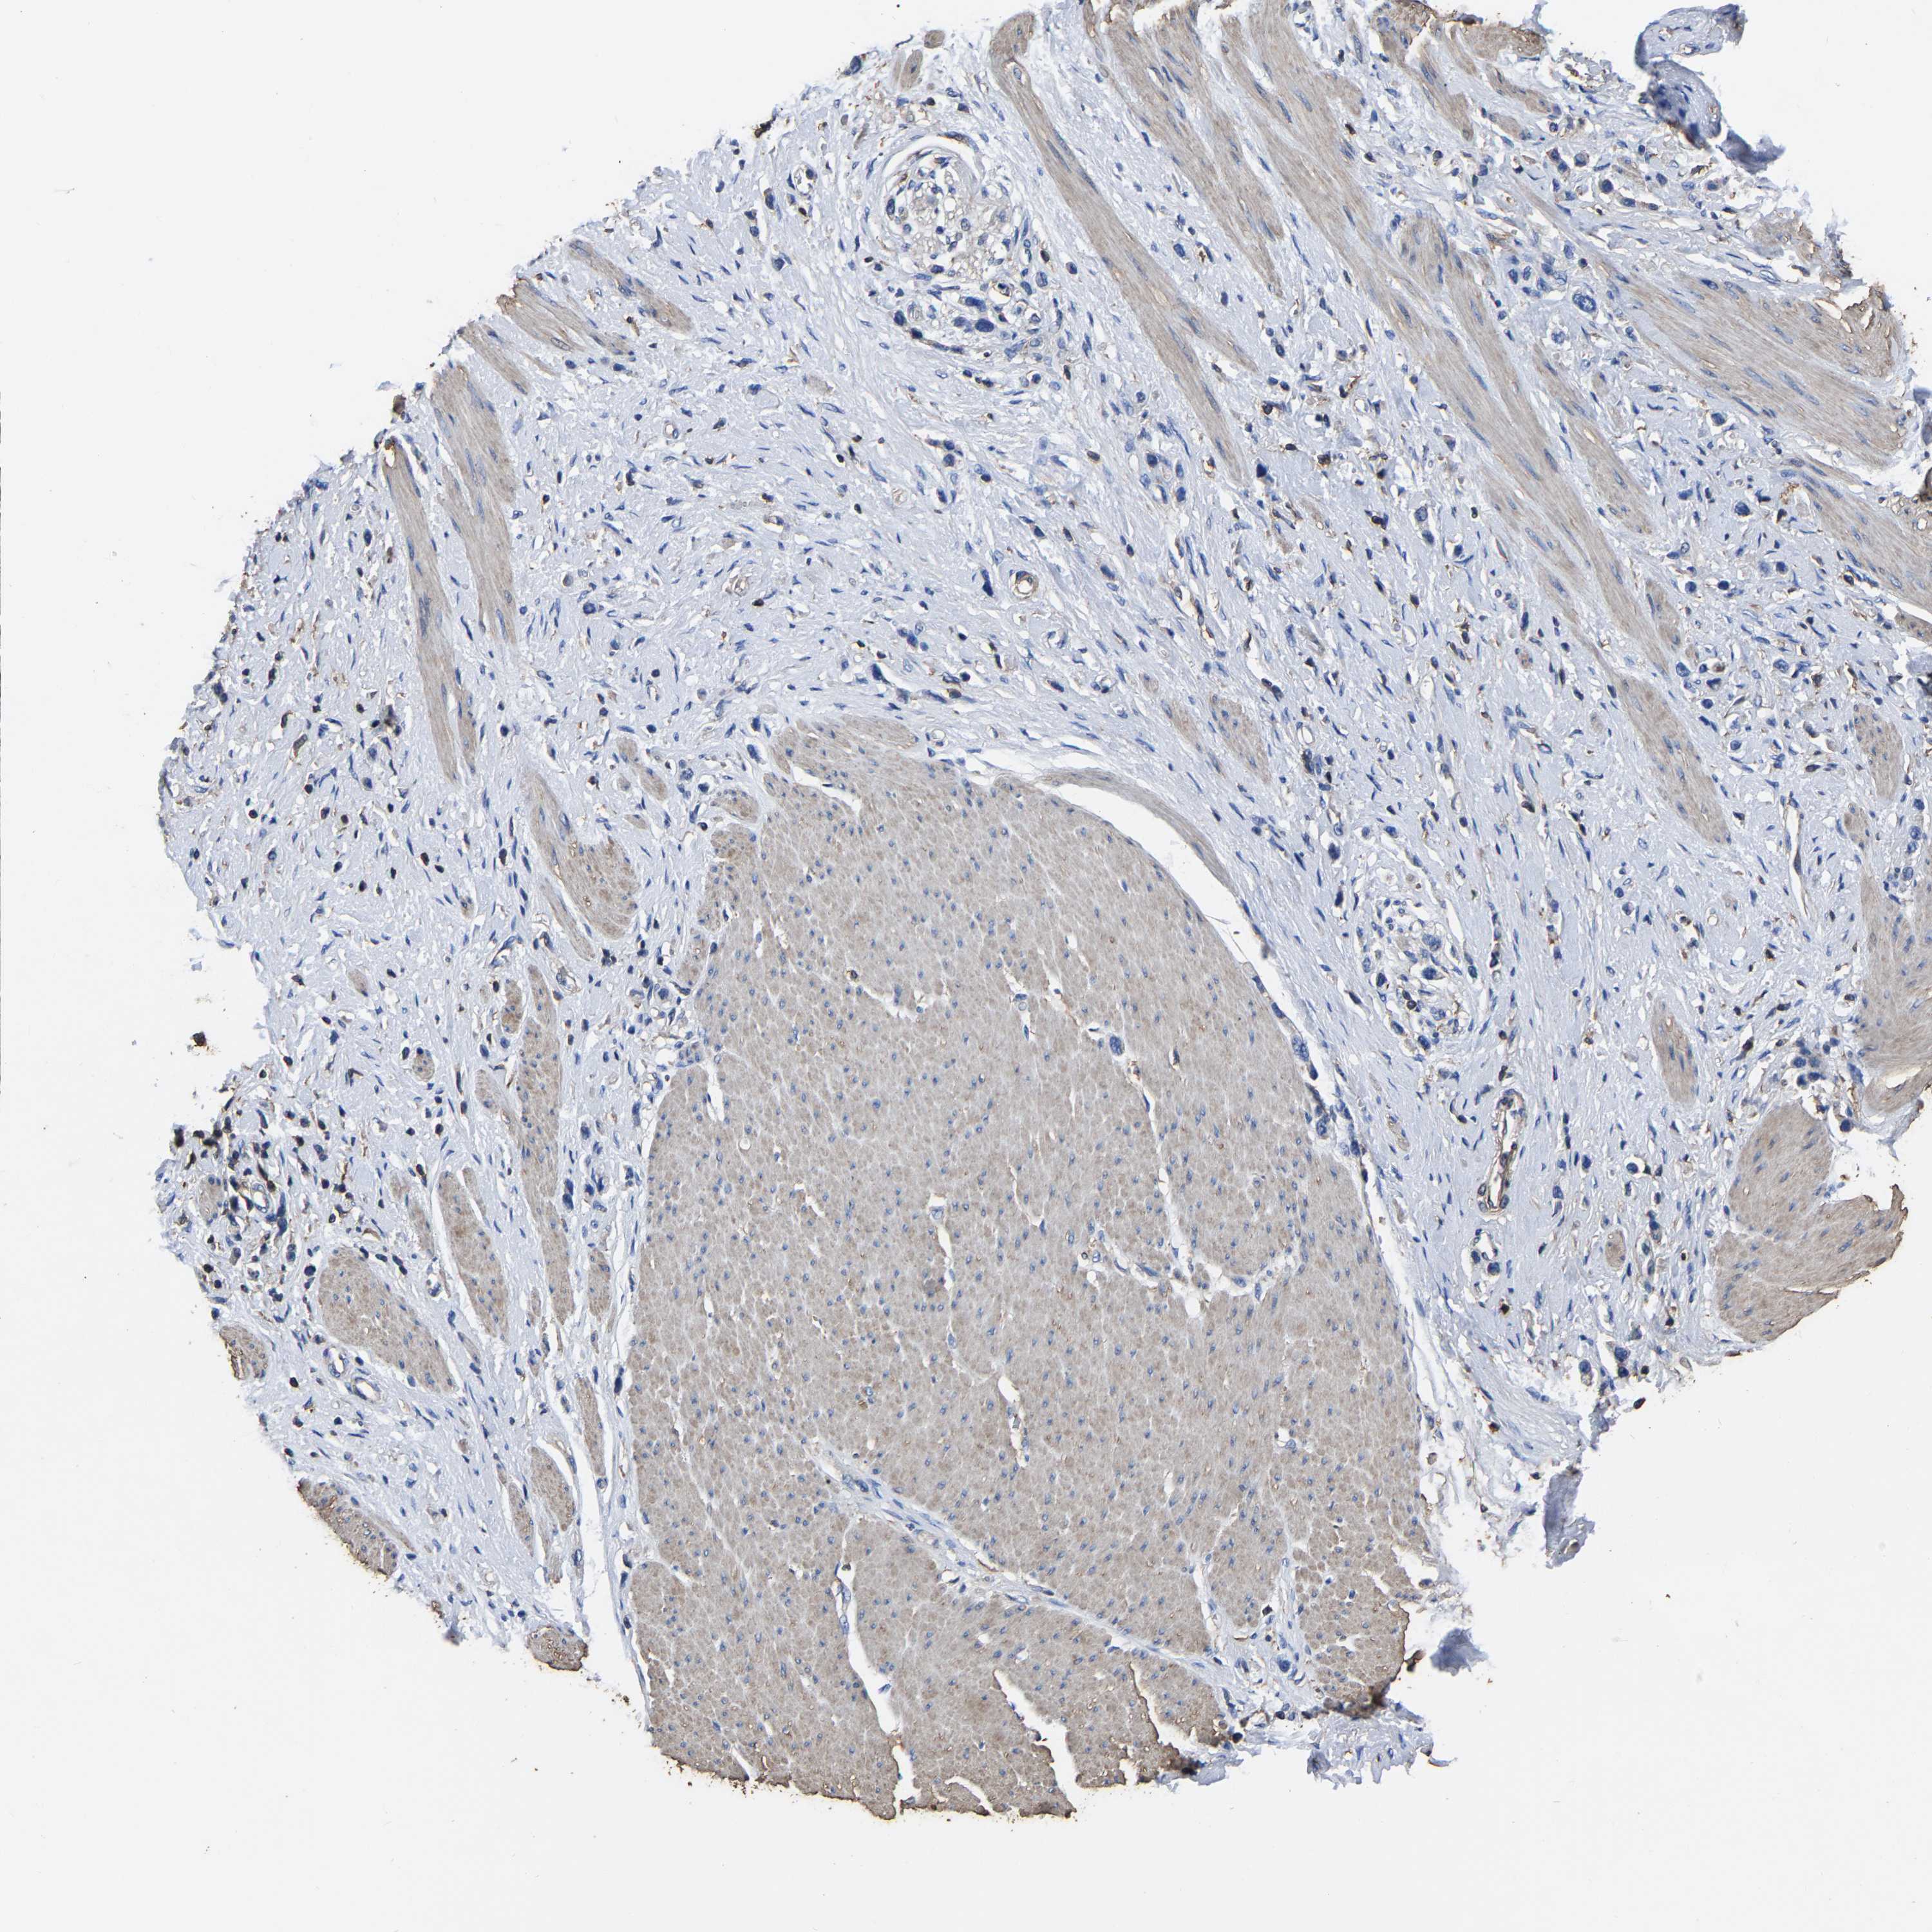

STOMACH CANCER - Protein expressioni

A mouse-over function shows sample information and annotation data. Click on an image to view it in a full screen mode. Samples can be filtered based on level of antibody staining by selecting one or several of the following categories: high, medium, low and not detected. The assay and annotation is described here.

Note that samples used for immunohistochemistry by the Human Protein Atlas do not correspond to samples in the TCGA dataset.

Antibody stainingi

Antibody staining in the annotated cell types in the current human tissue is reported as not detected, low, medium, or high, based on conventional immunohistochemistry profiling in selected tissues. This score is based on the combination of the staining intensity and fraction of stained cells.

Each image is clickable and will lead to virtual microscopy that enables deeper exploration of all samples and also displays staining intensity scores, fraction scores and subcellular localization as well as patient and tissue information for each sample.

Antibody HPA003004

Antibody HPA005819

Staining

High

Medium

Low

Not detected

Intensity

Strong

Moderate

Weak

Negative

Quantity

>75%

75%-25%

<25%

None

Location

Nuclear

Cytoplasmic/membranous

Cytoplasmic/membranous,nuclear

Adenocarcinoma, NOS